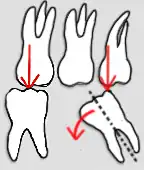

Wurzelform

Eine günstige Wurzelform weisen Zähne mit gespreizten Wurzeln auf, wie sie in der Abbildung an den Molaren zu sehen sind. Ebenso erhöht sich die Pfeilerwertigkeit durch die Form der einzelnen Wurzel, die im günstigen Fall eine zylindrische Form aufweist (in der Abbildung der zweite Zahn von links – Eckzahn 23). Ungünstig sind konisch zulaufende und kurze Wurzeln.

Furkationsgrad

Als Bifurkation (bei zweiwurzligen Zähnen) oder Trifurkation (bei dreiwurzligen Zähnen) wird die Aufteilungsstelle der Zahnwurzeln bei mehrwurzeligen Zähnen bezeichnet. Beim parodontal gesunden Zahn liegen sie innerhalb des Kieferknochens und sind weder sicht- noch sondierbar. Bifurkation und Trifurkation werden in vier Furkationsgrade eingeteilt. Eine freiliegende Furkation, die durch parodontalen Knochenabbau entstanden ist, bildet einen potentiellen Entzündungsbereich, der oftmals schwer zu reinigen ist. Je nach Ausprägung kann eine freiliegende Furkation die Pfeilerwertigkeit reduzieren.[12]

1) Freiliegende Bifurkation (Pfeil);

2) Prämolarisierung und Wurzelkanalbehandlung; 3) Zustand nach Überkronungen mit Stiftaufbauten;

(Darstellung durch Bildbearbeitung);